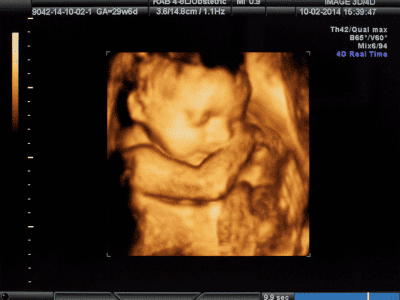

Exames pré-natais no 1° trimestre e 2º trimestre

A ultrassonografia obstétrica inicial (Transvaginal): realizada para confirmar a data da gestação, verificar o desenvolvimento do embrião dentro do útero e determinar se a gravidez é única ou de gêmeos.

Entre a 11ª semana e a 13ª semana e 6 dias, recomenda-se realizar a ultrassonografia morfológica de primeiro trimestre. Esse exame é essencial para avaliar o risco de o feto apresentar síndrome cromossômica, como a síndrome de Down.

Já no 2º trimestre, é realizada a ultrassonografia com foco em descobrir o descobrir o sexo do bebê.

A partir daí são continuados os exames periódicos para acompanhar o desenvolvimento do bebê como um todo, que são orientados pelo médico obstetra.